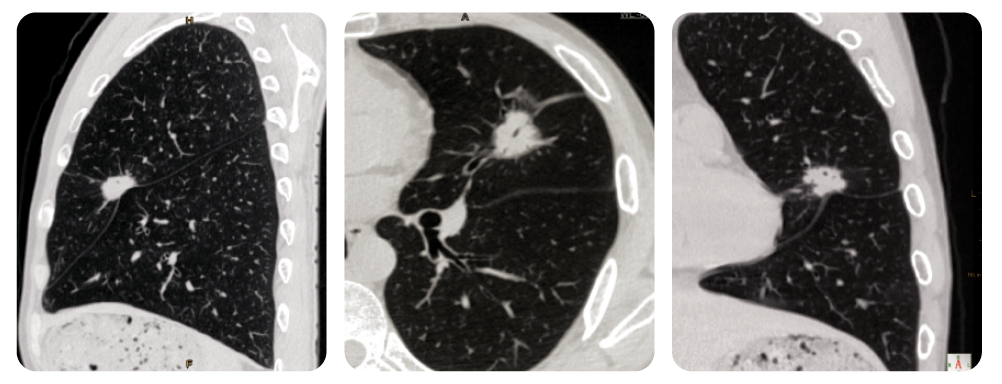

Imagini Pulmonare de Înaltă Rezoluție

Reformarea multiplanară arată un nodul pulmonar solitar în lobul superior stâng. Acest nodul prezintă margini neregulate, semne lobulate și pleurele golite. Acestea sunt indicatori clinici ai carcinomului.